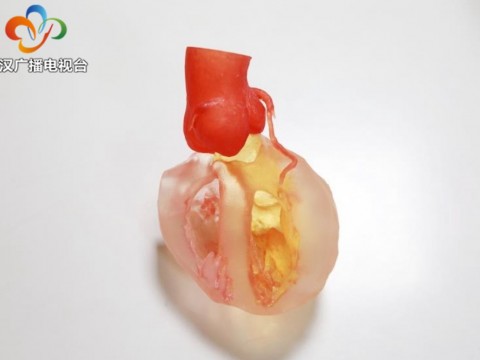

- “3D打印”技术助力治疗高难度主动脉瘤

- 3D打印“加持” ,17岁少年精准实施二次心脏手术